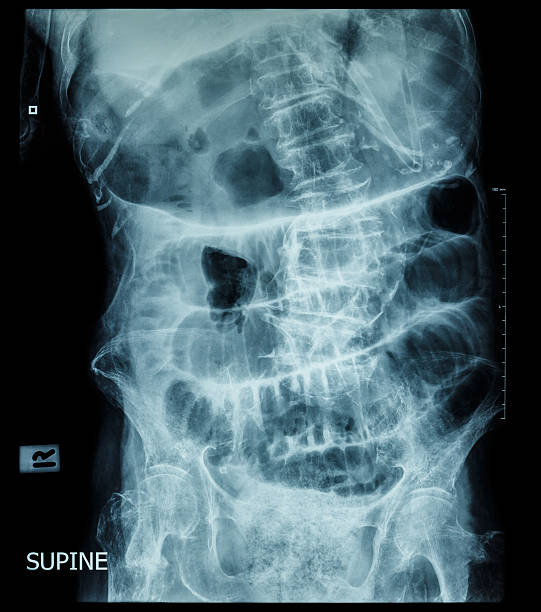

변비

장폐색으로 인한 변비는 대장 내부에서 대변이 막혀서 대변을 배출하기 어려운 상황을 말합니다. 대변이 막혀 있어서 배출이 어렵고, 배출하려고 노력하면 통증이나 출혈 등의 증상이 나타날 수 있습니다. 대장 내부에서 대변이 막히는 원인으로는 대장암, 섬유화, 협착, 분절증 등이 있을 수 있습니다.